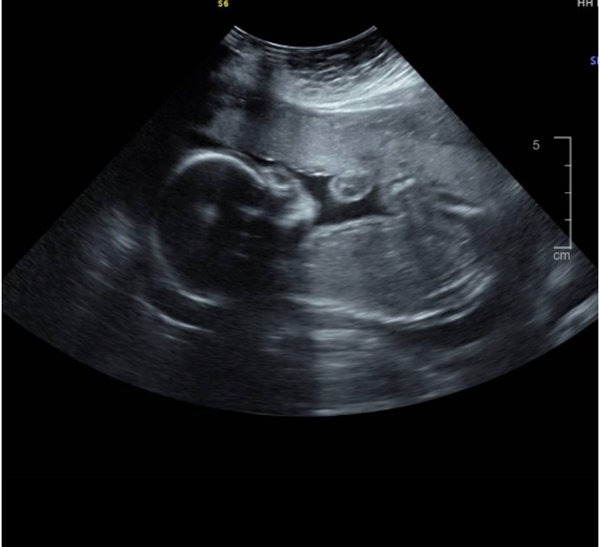

ولد ماشاءالله

اذا طلع ولد صدق ادعيلي لا تنسين تكفين

كيف تعرفين اذا ولد او بنت